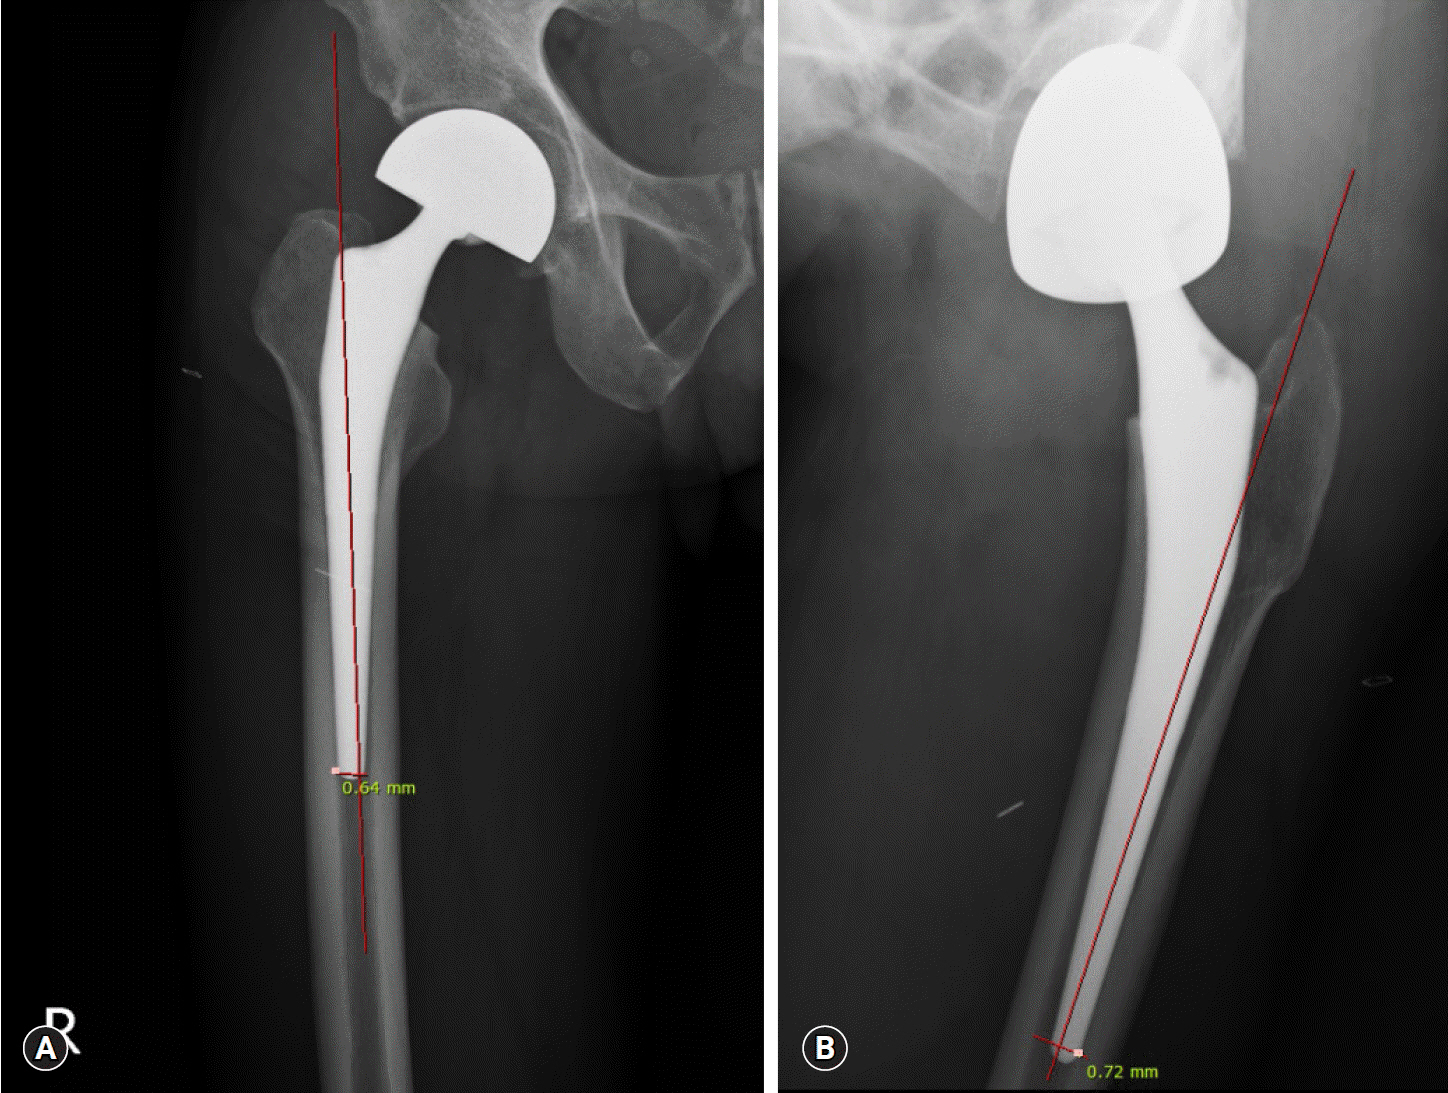

Postoperative pain occurring after hip arthroplasty has become common since the expanded use of cementless femoral stems. The characteristic pain develop in the anterolateral thigh area. This study aimed to predict anterior thigh pain based on the measurements of postoperative anteroposterior (AP) and lateral (Lat) radiographs of the hip joint.

The present study included 26 patients (29 hips) who underwent total hip replacement or bipolar hemiarthroplasty between March 2010 and May 2016, whose complete clinical information was available. AP and Lat radiographs of the affected hip were taken on the day of surgery and 1 and 6 months postoperatively. Patients with improper radiographs were excluded. The distance from the femoral stem to the nearest cortical bone in the distal region of the stem was measured. The patient group with a visual analog scale (VAS) score of ≥6 points was designated as patients with anterior thigh pain.

Sex, age, weight, height, body mass index, and bone mineral density in the lumbar spine and femur did not have a significant effect on postoperative VAS scores (p>0.05). Presence of contact between the femoral stem and cortical bone was associated with postoperative anterior thigh pain.

Hip AP and Lat radiographs are usually taken to confirm fixation and alignment of the femoral stem after hip arthroplasty. The measurement method introduced in this study can be utilized for predicting anterior thigh pain after hip arthroplasty.